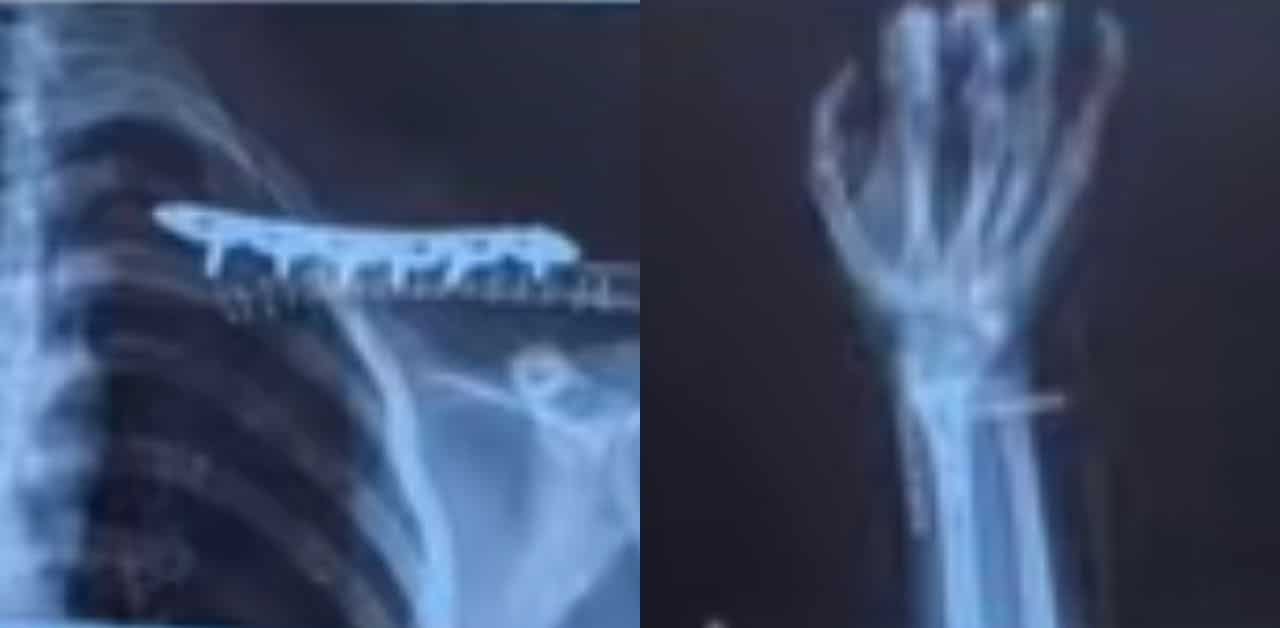

The impact caused the motorcycle to slide across the road and collide with La Min Khaing, who was also riding a motorcycle at the time. The male motorcyclist was pronounced dead at the scene, while La Min Khaing sustained serious injuries, including a broken wrist and a fractured clavicle.

She also shared that doctors told her the injuries could take more than two years to fully heal. The physical limitations affected her daily life, preventing her from exercising and from performing laboratory experiments required for her studies.